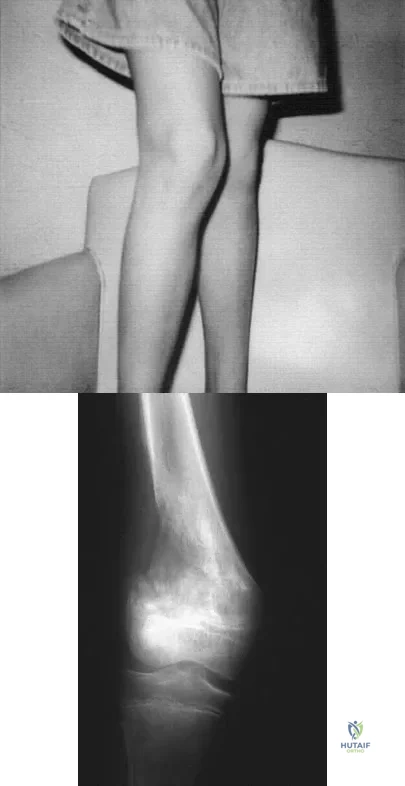

A 13-year-old girl is referred for a painful progressive valgus deformity of the right knee. Examination reveals an antalgic gait with an obvious valgus deformity. The right distal femur has a palpable, tender mass with erythema and warmth. Figures 4a and 4b show a clinical photograph and a radiograph. Management should consist of